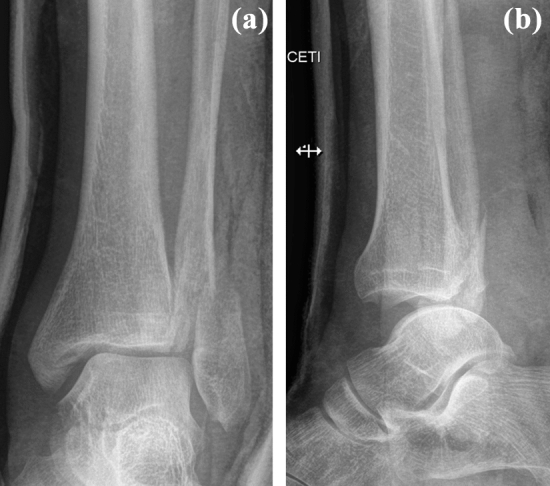

A 39-year-old man slipped while running in the woods and severely twisted his left ankle. Immediately after the injury he experienced sharp pain in his left foot and ankle and was unable to walk. He was taken to a hospital and diagnosed with a Bosworth fracture of the left ankle 3 h after the injury. Radiographs showed a Weber type B fracture of the fibula, with a widened medial clear space and a concomitant fracture of the posterior malleolus. The presence of a Bosworth fracture-dislocation was suggested by overlap of the tibia and the proximal fragment of the fibula in the anteroposterior view, posterior subluxation of the talus and tibiofibular dissociation in the lateral view (Fig. 1).

Fig. 1.

Initial anteroposterior and lateral radiographs with typical signs of a Bosworth fracture-dislocation: a overlap of the distal tibia and fibula, and b posterior dislocation of the talus and tibiofibular dissociation with the fibula being displaced posteriorly